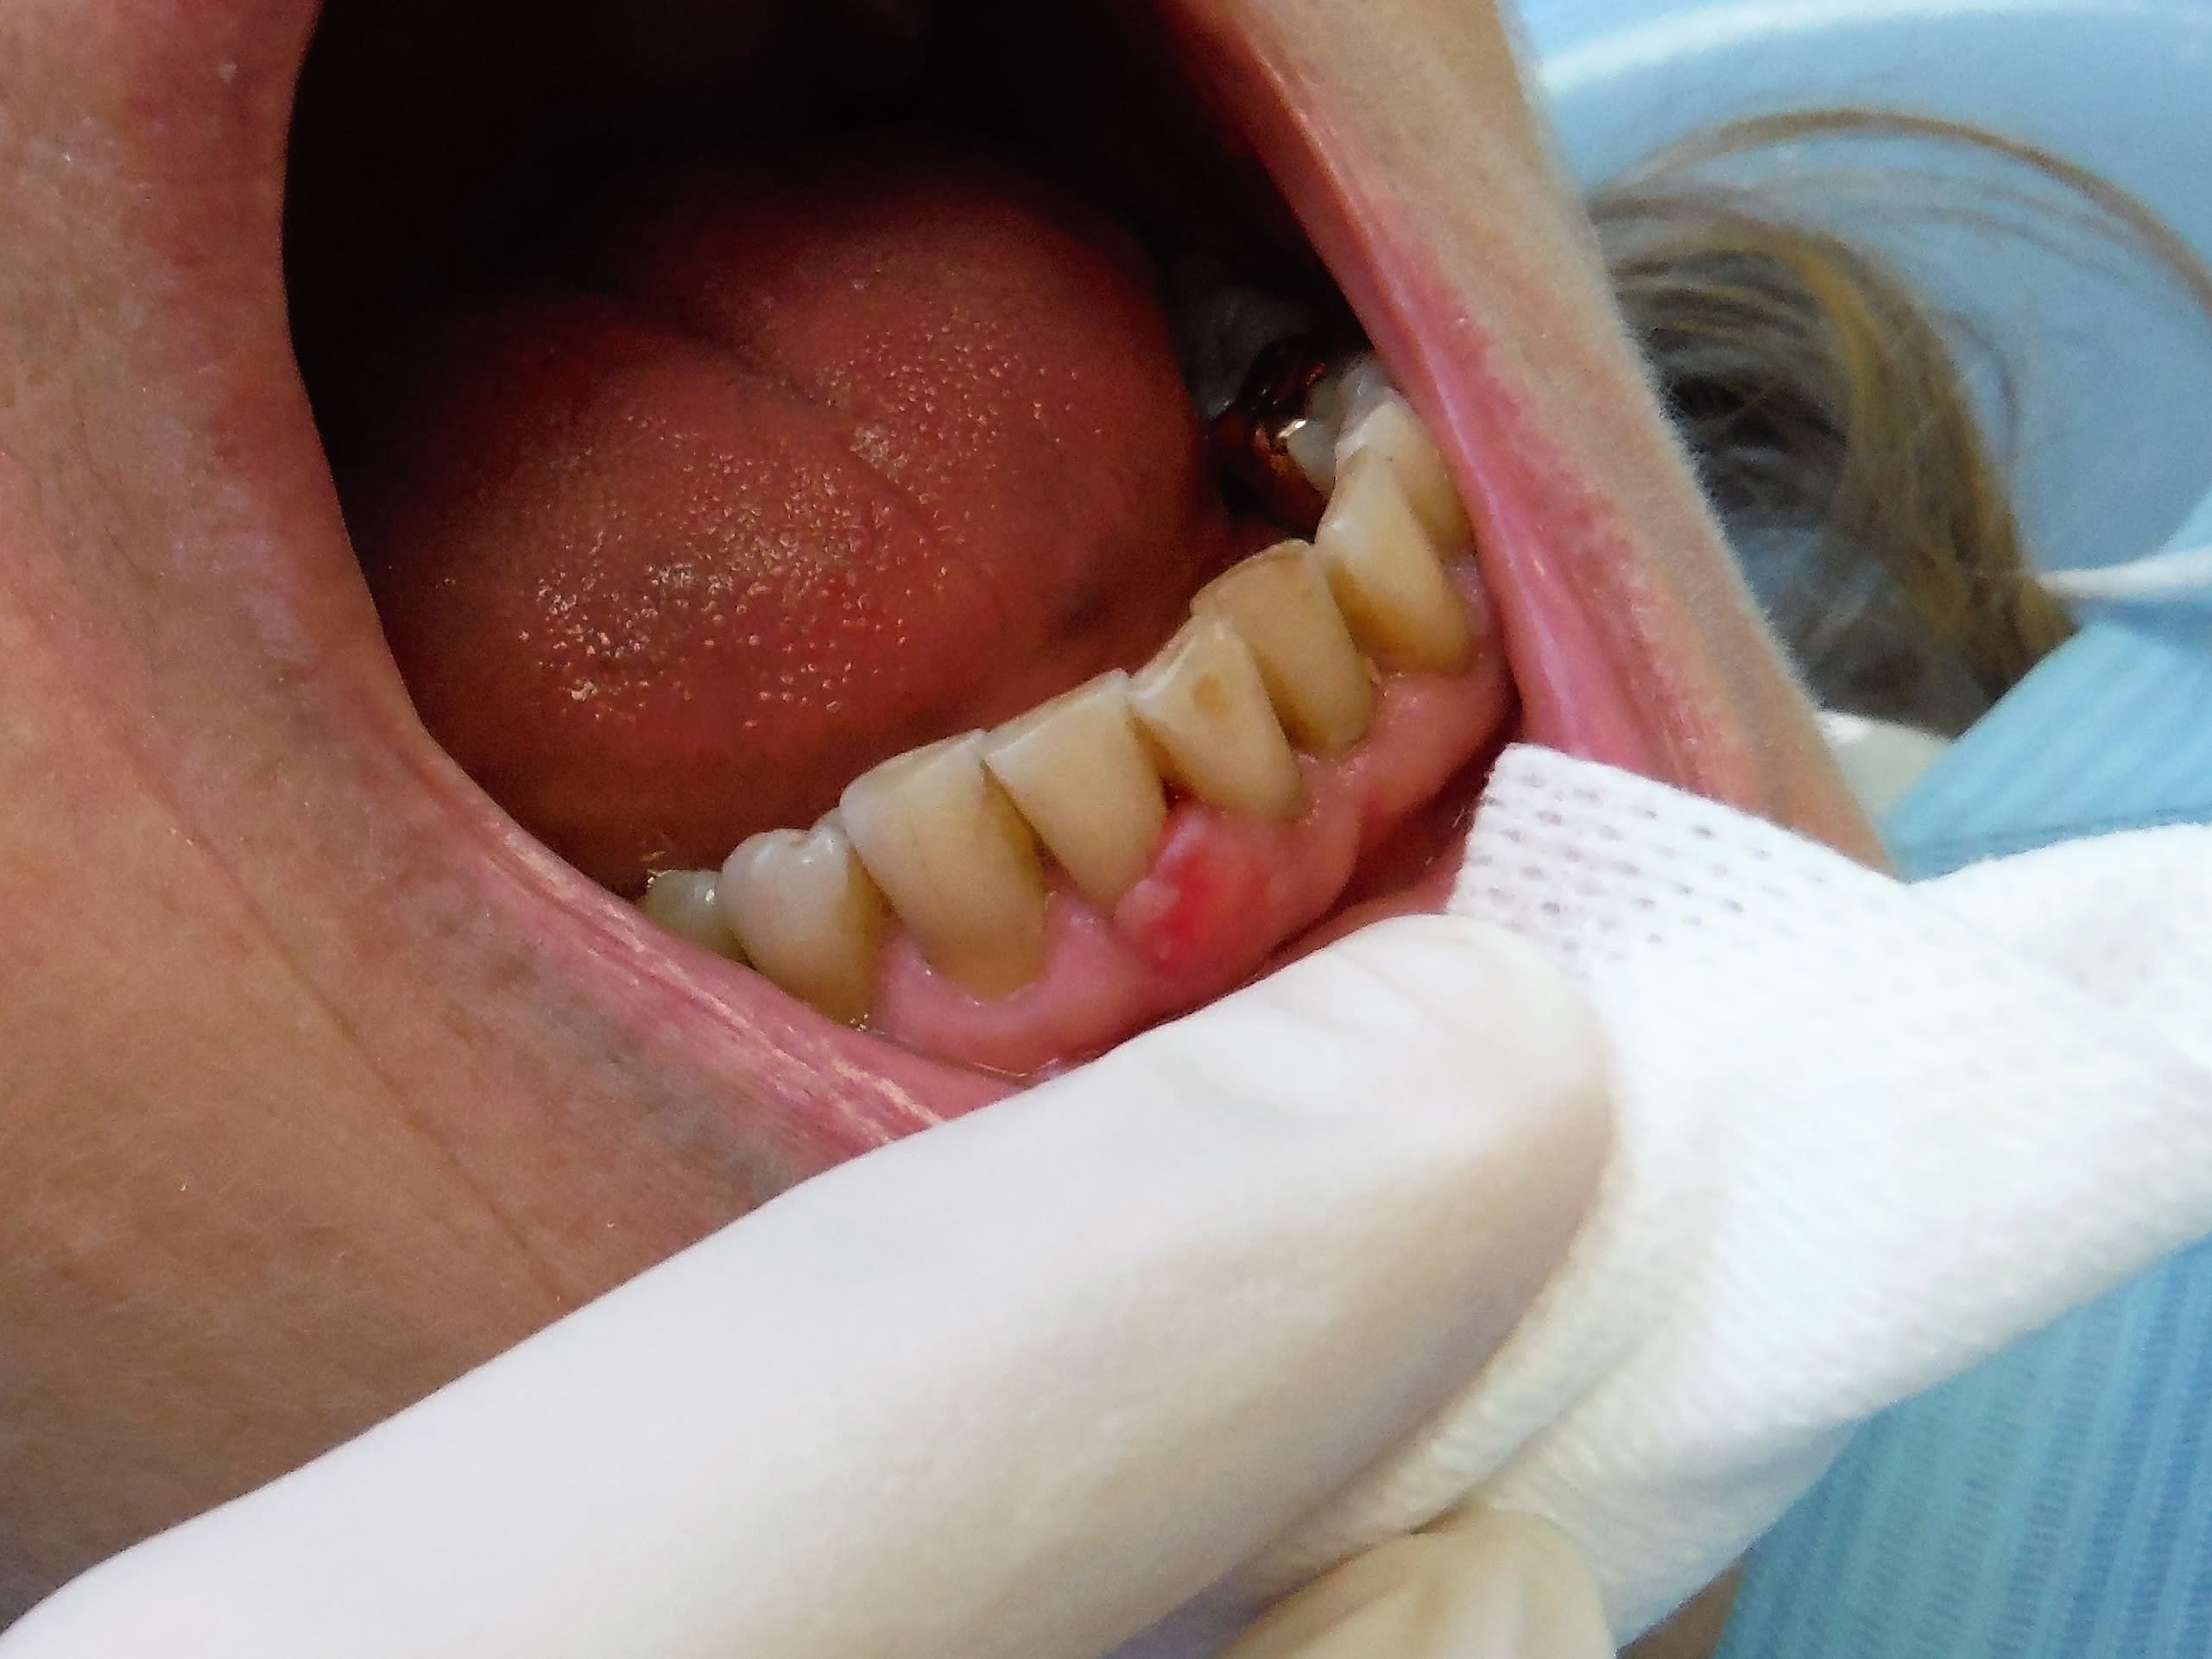

Là en revanche... je sèche.

Avec une compresse pour mieux y voir:-)

Et le bobo à la gencive t'en dis quoi ?